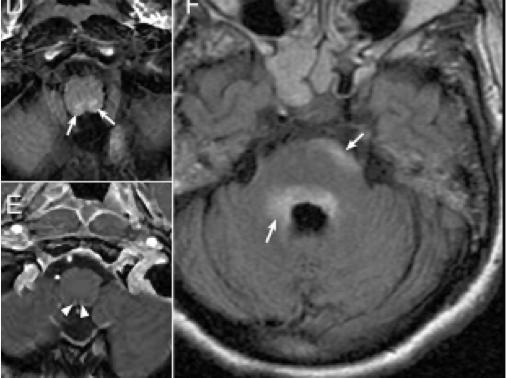

3. NMOSD 脑干MRI:四脑室周围,分布集中